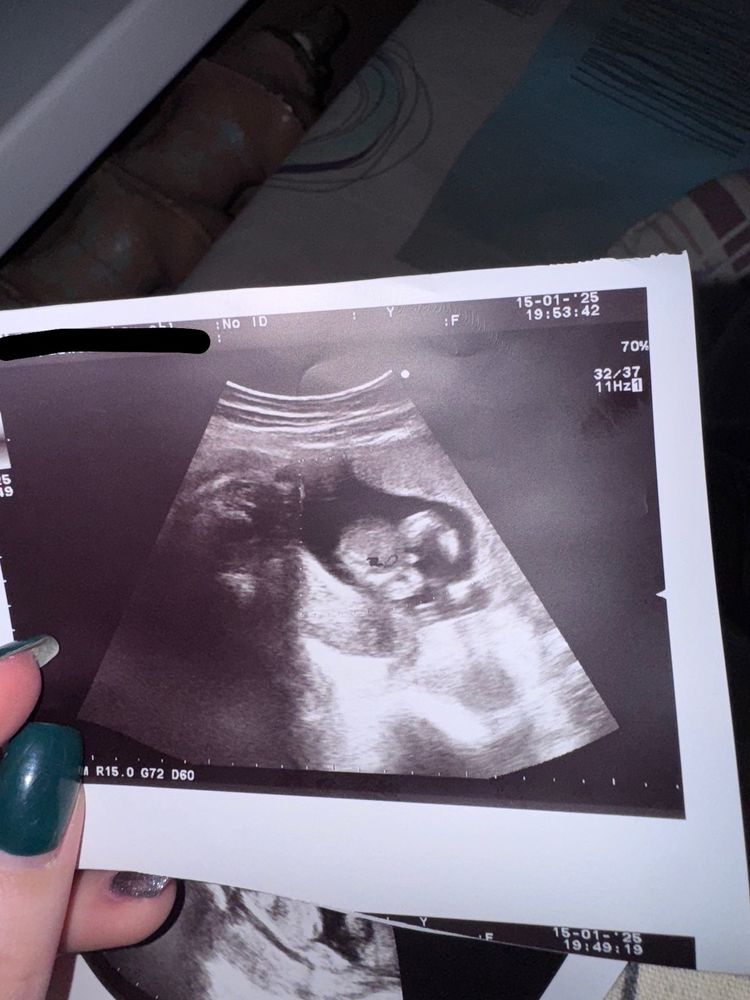

Всем привет! Кого видите на фото? Девочку или мальчика или может всё таки это пуповина?

врач сказала, что вроде мальчик

Очевидно мальчик, прекрасно видно мужской половой орган между ног 👌🏽